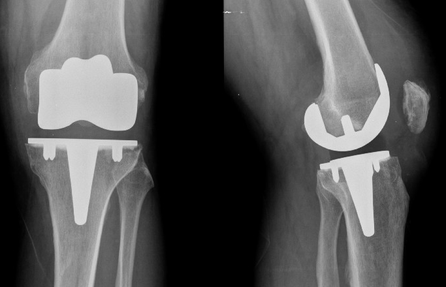

Genou